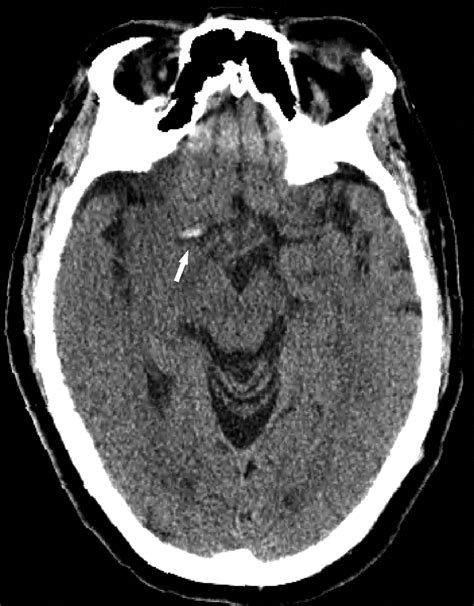

Diagnosing head blood clots requires specialized imaging techniques. Because standard physical exams cannot detect these clots, doctors typically utilize high-tech scanning methods.

• MRI (Magnetic Resonance Imaging): Often paired with an MRV (Magnetic Resonance Venography) to specifically visualize the veins in the brain.

• CT Scan (Computed Tomography): A CT venogram is highly effective at identifying blockages in the venous sinuses.